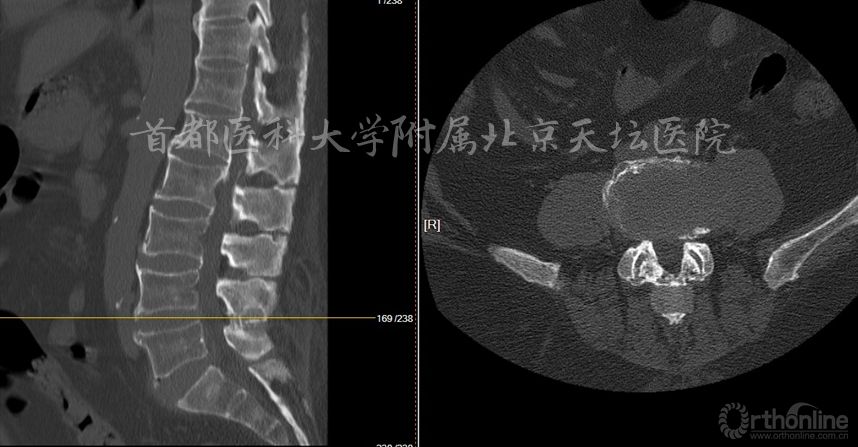

影像资料:

诊断:

• 腰椎管狭窄症(双侧神经根管狭窄)

• 棘突间植入物术后(Wallis)

• 棘突骨折

• 骨质疏松症

针对此病例,各位专家的讨论焦点主要落在棘突间植入物的疗效究竟如何上。天坛医院刘宝戈教授针对这个病例指出,患者曾在外院行棘突间植入物手术,术后不久再次出现症状,翻修手术如何进行?这需要细致的考量。针对该例老年患者,他们最终选择了微创的治疗方式,基于术前精确责任节段的定位,术后疗效满意。